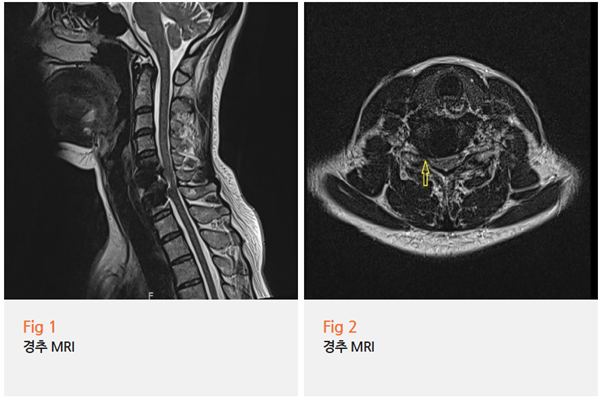

MRI와 근전도 검사를 다시 해보니

그림9.png 촬영 일시: 2025.06.26

✅ 경추 5, 6, 7번 디스크 문제

✅ 흉추 1번 디스크 문제

✅ 이로 인한 신경압박

이렇게 명확하게 나왔어요.